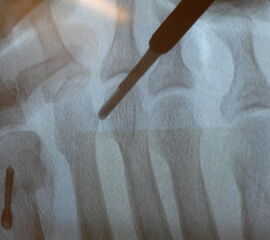

Nach Bestimmung der korrekten Osteotomiehöhe wird mit dem MIS-Mikrotom eine je nach Seitendominanz des Operateurs dorsolaterale oder dorsomediale 3-4mm lange Längsinzision parallel zu den Strecksehnen auf Höhe des metadiaphysären Überganges am distalen, zu osteotomierenden Metatarsale  durchgeführt. Im Anschluss erfolgt die Präparation mit einer schlanken, im Schaft gebogenen und vorne stumpfen Raspel oder mit einem gebogenen Klemmchen. Die Präparation erfolgt unter stetigem  Knochenkontakt mit der Kortikalis des Metatarsale medial oder lateral bis nach plantar unter die Beugesehenen.  So kann der Weg für die Fräse vorpräpariert und eine Weichteilinterposition zwischen Fräse und Knochen vermieden  werden.

Jetzt erfolgt das Einbringen der Fräse im 45°-Winkel von distal dorsal nach proximal plantar. Auf steten Knochenkontakt mit der Kortikalis zur Vermeidung eines Weichteilinterponates sollte geachtet werden. In unserer Abteilung erfolgt vor Beginn der Osteotomie nun eine nochmalige Lagekontrolle der Fräse unter dem Bildwandler im dorsoplantaren Strahlengang. Eine zusätzliche laterale Aufnahme kann die Tiefe der eingebrachten Fräse in Bezug auf das zu osteomierende Metatarsale zeigen, ebenso ermöglicht sie eine Kontrolle des 45°-Winkels.